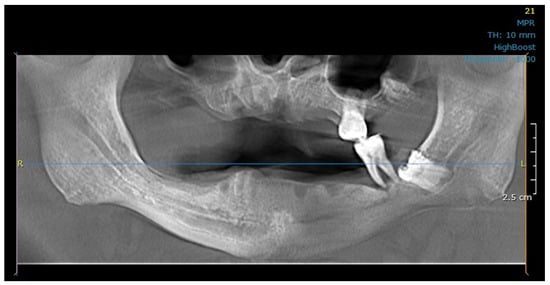

2.3. Modeling